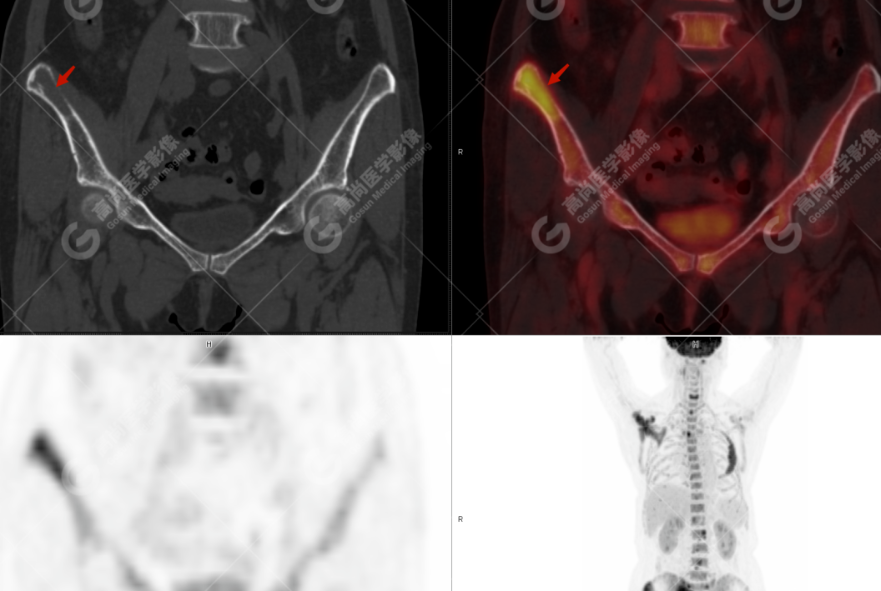

颅骨、寰椎前弓左侧份、第 6 颈椎、双侧肩胛骨(右侧为著)、左侧第 4 肋骨、第 1 胸椎、第 4 胸椎、第 2 腰椎及附件、第 4 腰椎及附件、骶骨、右侧髂骨、左侧坐骨结节、左侧股骨颈、双侧股骨小转子等均不同程度骨质吸收、破坏,其中右侧肩胛骨、左侧第 4 肋骨及骶骨右侧份软组织肿块影形成,上述病变均考虑恶性肿瘤(血液系统来源,多发骨髓瘤可能性大),建议右侧髂骨翼穿刺活检明确。

(4)PET-CT 影像表现:在溶骨性破坏区出现相重叠的 18F- FDG 高代谢区;通常呈弥漫性高代谢区。